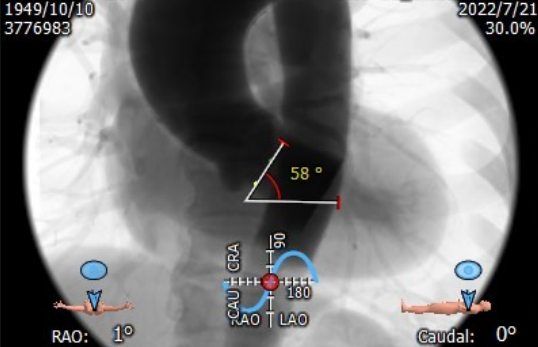

横心位:58°

• 右冠开口尚可,瓣叶较长,若选择24瓣膜,冠脉风险低;若选择27瓣膜,则存在冠脉风险,建议球扩关注冠脉是否需要保护;

• 横心位角度较大,在过弓时或可遇到困难;